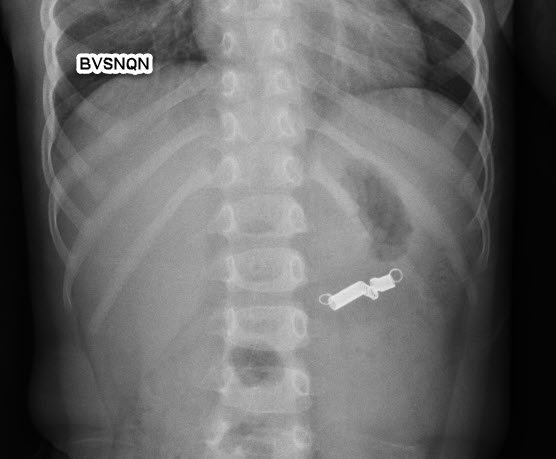

Kết quả chụp X-quang cho thấy hình ảnh dị vật cản quang ngang mức đốt sống L1. Qua hội chẩn chuyên khoa, các bác sĩ quyết định Chỉ định nội soi tiêu hóa cấp cứu gắp dị vật cho bệnh nhi. Kết quả nội soi ghi nhận di vật hình lò xo kim loại, kích thước 3x1cm tại vị trí tá tràng đã được gắp ra an toàn